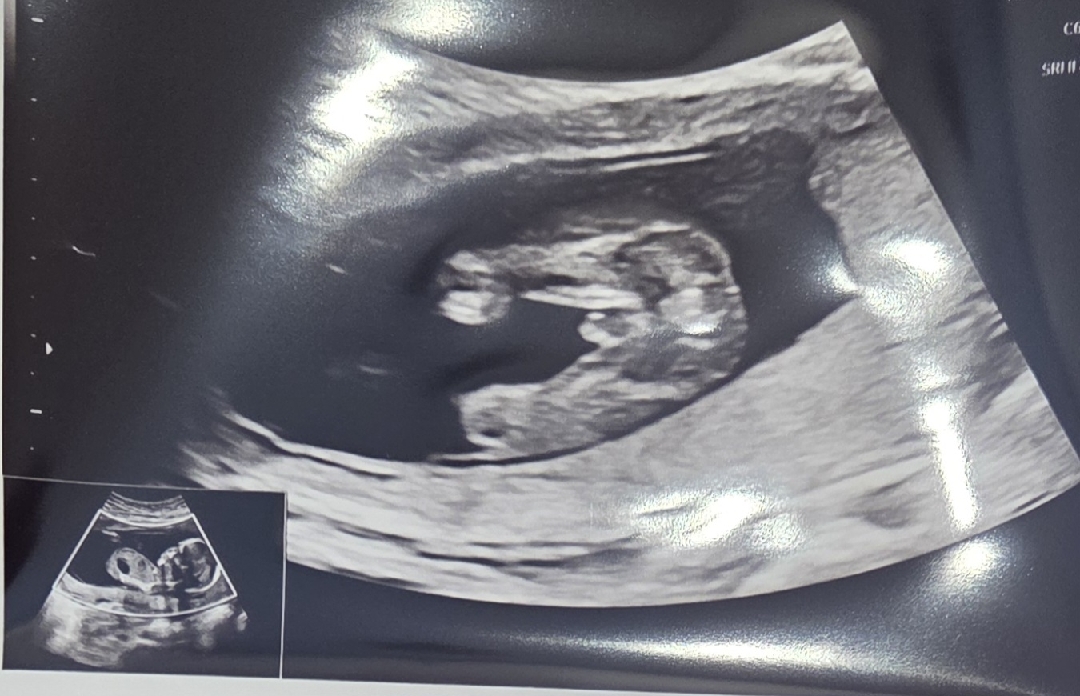

아들? 딸?

16주입니다!

아들요 !

누가 봐도 아들같아요 🤗

아들같네용:)

그쵸 너무 튀나온거같죠..?:)